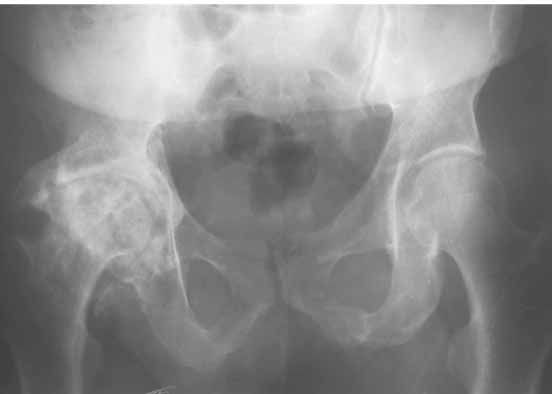

Дорогие коллеги.Мой хороший товарищ, сам травматолог-ортопед, прооперирован 1,5 мес назад. Естественно, начались проблемы. Хотелось бы узнать ваше мнениеи, главное,что делать дальше... Итак:Мужчина 50 лет.Д-з: Посттравматический деф.артроз правого тазобедренного сустава с выраженным болевым синдромом, стойкой комбинированной контрактурой иукорочением 3 см. Анамнез: 10 лет назад - сочетанная травма головы, груди, конечностей, таза... перелом заднего края вертлужной впадины и вывих бедра справа.Лечился консервативно. 25.05.94 - операция тотальное эндопротезирование правого тазобедренного сустава бесцементным эндопротезом (чашка Споторно 52, ножка Вагнера 225/21, головка L), дополнительная фиксация в кокситной гипсовой повязке в течение 3 нед. Спустя месяц после операции при поворачивании на бок в кровати произошел вывих головки эндопротеза. Под наркозом вывих вправили. Вот 10 дней лежит в постели. Что необходимо делать? Рентгенограммы до операции и после. Рентгенограммы в положении вивиха у меня отсутствуют. Ну наверное они и не столь важны, ведь вывих-то вправили. Учреждение и фамилию пациента, нашего коллеги, называть не буду. Он попросил меня собрать мнения - как ему жить дальше. Заранее благодарен. С уважением Александр Артемьев

Для ответа на Ваши вопросы нужна, как минимум, обзорная

рентгенограмма таза в прямой проекции - многое станет ясно без слов.

Первые впечатления:

1. Вертикальное положение чашки;

2. Нарушение угла антеверсии ножки (судя по изображению малого вертела

на послеопреационной рентгенограмме).

3. Комбинация этих двух причин.

4. Видимо, тенденция к вывиху была уже на столе - вот Вам и кокситная повязка с надеждой на фиксацию протеза рубцом.

Обзорная рентгенограмма таза просто необходима. Удивительно, почему она не сделана сразу же после установки протеза.

Сан Саныч,

Консультировать вывихи по рентгенограммам, не зная хода операции, дело не очень благодарное. Я думаю, что с датой операции Вы ошиблись и это был 2004 год? Тем не менее. Настораживают два фактора. Первое - не видно большого вертела. Если с мышцами обошлись грубо и их отсекли, то это очень грустно и нужна "связанная" пара, т.н. "constrain cup". Смущает хорошо прослеживаемый малый вертел и небольшая ретроверсия чашки. Возможно это (избыточная ретроверсия ножки и чашки) могло послужить причиной вывиха. Обычно гипсовая повязка после операции не накладывается, значит, были глубокие сомнения у оперировавшего хирурга. В этом случае - ревизия с перестановкой как минимум - ножки, а как максимум - обоих компонентов.